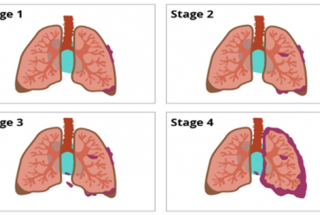

Theo Globocan 2020, tại Việt Nam, ung thư phổi đứng thứ 02 trong các bệnh ung thư thường gặp, chiếm tỷ lệ 14,4% tương ứng 26.262 case mắc mới mỗi năm ở cả hai giới, chỉ sau ung thư gan. Ung thư phổi không tế bào nhỏ là nhóm ung thư phổi thường gặp tại Việt Nam cũng như trên thế giới (chiếm ~80%). Đa số bệnh nhân được phát hiện trong giai đoạn muộn và tiên lượng xấu, thời gian sống thêm rất ngắn. Việc chẩn đoán sớm và điều trị hiệu quả ung thư phổi là mục đích chính yếu của bác sĩ chuyên ngành ung thư, giúp tăng thời gian sống thêm và chất lượng cuộc sống cho người bệnh.